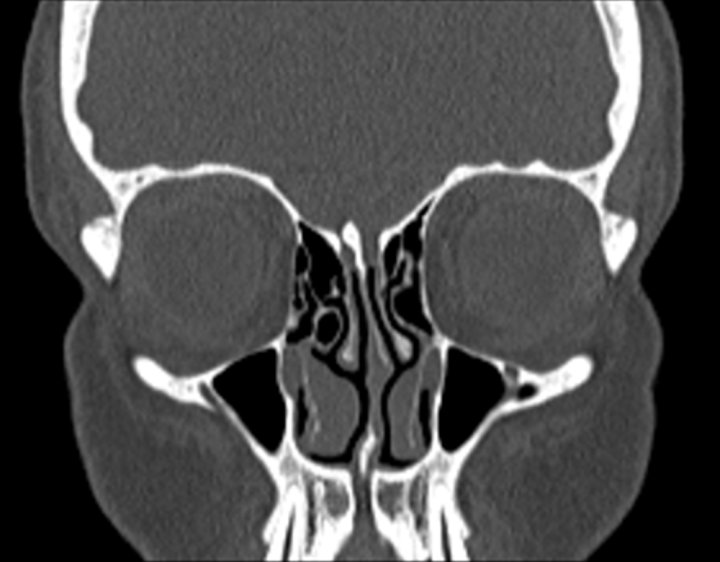

Click any image for labels.